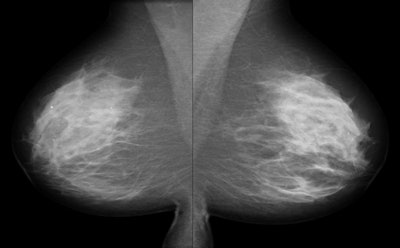

| Mediolateral oblique (MLO) views of a 56-year-old woman whose sister had breast cancer are normal (above). But automated breast ultrasound (below) showed a small mass in the left breast. This image is from a focused breast ultrasound exam, performed because of the finding detected on automated ultrasound. Biopsy confirmed a 10-mm invasive ductal carcinoma. All images courtesy of Dr. Judy Dean. |